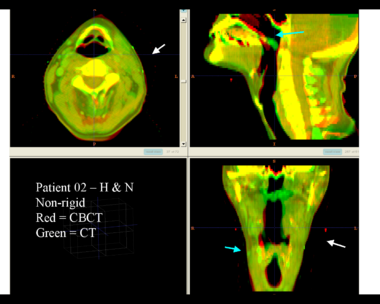

Here is another pertinent example for head and neck. In axial view, there appears to be some weight loss. Note the change in positioning of the mandible, and also the twisting of the cervical spine between scans. Also note the strong CT artifacts caused by dental fillings. In both examples, registration of the soft palette is worse using deformable registration than rigid registration, probably due to these artifacts.